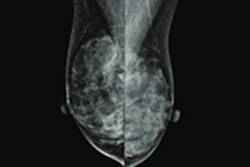

Premenopausal women with a family history of breast cancer have a higher chance of having dense breasts and experiencing increasing breast density, according to research published March 10 in JAMA Network Open.

Personal family history of breast cancer and mammographic breast density are both considered breast cancer risk factors. And while breast density generally decreases with age, recent research suggests that women who develop increased breast density over time are at higher risk.